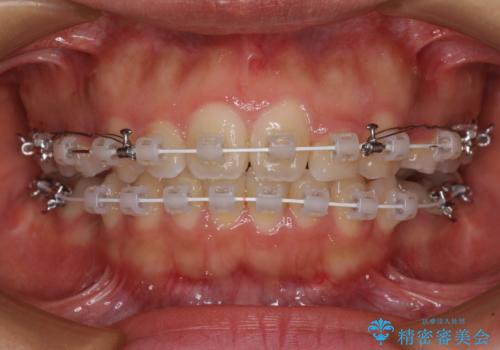

- 審美装置

- 2年2ヶ月

上顎抜歯のみでは奥歯の咬み合わせを改善することが困難であったため、途中で下顎小臼歯も抜歯をしました。

抜歯のタイミングが遅れると治療期間が長期化するため、速やかに抜歯の判断をし、2年強の期間で治療を終えることができました。